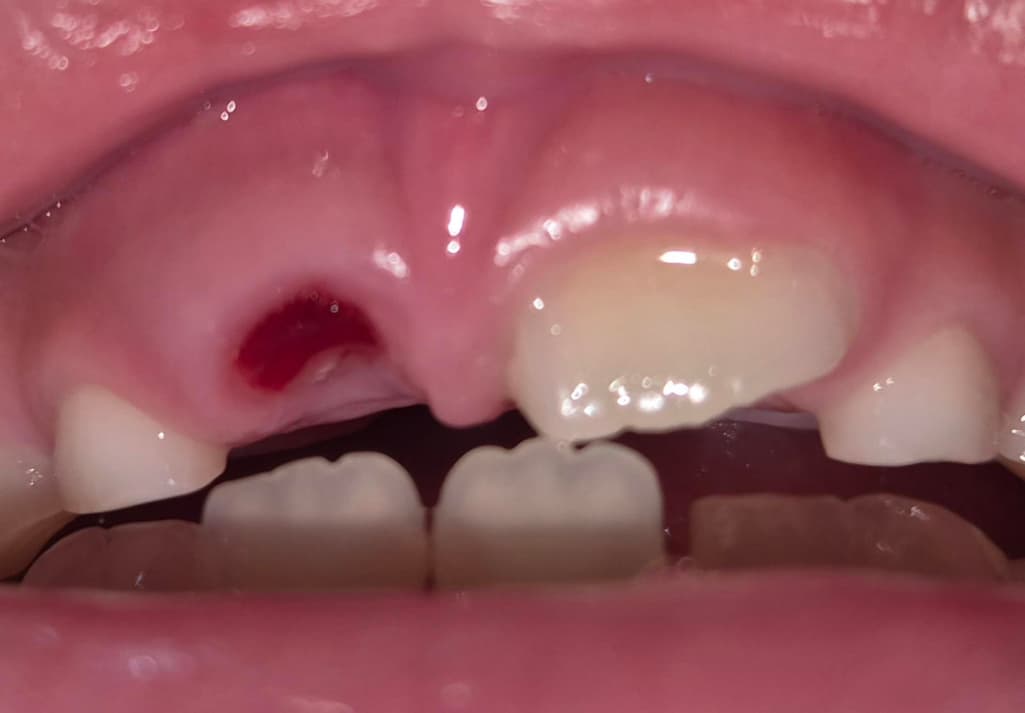

어제 아이 유치를 실을 이용해서 뺏고

지혈도 바로 되었는데 이빨을 찾았는데 정상적으로 뽑힌게 맞나요?

사진상으로는 문제 없이 잘 빠진 것으로 보이며 지혈 또한 잘 되어 있는 것으로 보여 괜찮아보입니다.

사진으로 봤을 경우에는 치아는 잘 나온 것으로 보입니다. 유치가 빠지고 났다면 영구치아가 잘 맹출되고 있는지를 확인하기 위해서 치과에서 진료를 받아보는 것이 좋습니다.

사진상으로 보면 아이의 유치가 잘 발치가 된거 같습니다. 크게 걱정은 안하셔도 될것같습니다.

보통 유치는 흔들려서 빠졌다면 뿌리가 많이 녹아 짜리몽땅한 형태로 빠져나옵니다 뿌리가 남지 않았을까 크게 걱정하진 않으셔도 됩니다. 혹여 남았더라도 아래 영구치가 밀고 올라올겁니다.